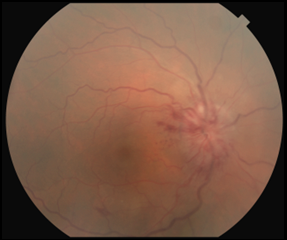

Best-corrected visual acuity (BCVA) measured 20/200 in the right eye and 20/20 in the left eye. Pupils were round and reactive with a grade 1 afferent pupillary defect (APD) in the right eye. Color vision testing with Hardy Rand Rittler pseudoisochromatic plates measured 4/12 in the right eye and 12/12 in the left eye. Results of extraocular motility testing, cover test and confrontation visual field testing were normal. Slit lamp examination was unremarkable. Intraocular pressure was 12 mmHg in each eye by Goldmann applanation tonometry. Dilated funduscopic examination of the right eye revealed a swollen elevated right optic nerve with obscuration of the optic disc margin that was worse along the temporal disc margin with associated neuroretinal rim hyperemia and hemorrhages. The cup-to-disc ratio of the right optic nerve was difficult to assess, and no evidence of Paton’s folds was seen. A small flame-shaped retinal hemorrhage was noted along the inferior temporal arcade in the right eye. Mild macular retinal pigment epithelial changes and retinal vessel tortuosity were also noted in the right eye (Figure 1A). Funduscopic examination of the left eye was unremarkable (Figure 1B).

![]() Figure 1A. Color fundus photograph of the right eye at initial presentation revealed obscuration of the optic disc margin, worse temporally, with associated neuroretinal rim hyperemia. No signs of Paton’s folds or overlying disc drusen were seen. A small flame-shaped retinal hemorrhage was seen along the inferior-temporal arcade (arrow). Click to enlarge |